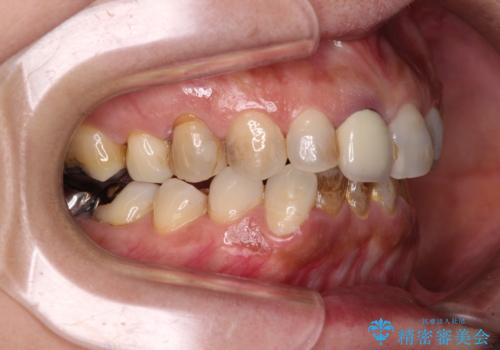

- 上下前歯のデコボコと、治療途中の歯を気にして来院された患者様です。

ご家族がインビザラインにて矯正治療を行っていたため、ご本人の希望によりインビザラインによるマウスピース矯正を行うこととしました。

根管治療が必要な歯は事前に処置を行った上で矯正治療を開始し、概ね歯列が整ったところでセラミッククラウンなどに置き換え、その後インビザラインを1セット使用して仕上げていくこととしました。